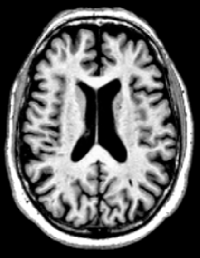

In this study, we use the baseline 1.5T T1-weighted MRI images of subjects from the ADNI-1 dataset [10]. The volumetric 3D MPRAGE protocol is used to acquire sagittal T1-weighted MRI images with an in-plane spatial resolution of 1.25×1.25mm21.251.25superscriptmm21.25\times 1.25~{}\mathrm{mm}^{2} and 1.2 mm thick sagittal slices. The imaging dataset contains baseline images from 695 participants including 200 Alzheimer’s disease, 231 cognitively normal, 164 progressive MCI, and 100 stable MCI. Figure 5 shows four samples from this dataset, and Table 1 presents the demographic and clinical information of subjects in ADNI-1.

Figure 5: Four samples from ADNI-1 dataset [10] (a) AD, (b) CN, (c) pMCI, and (d) sMCI